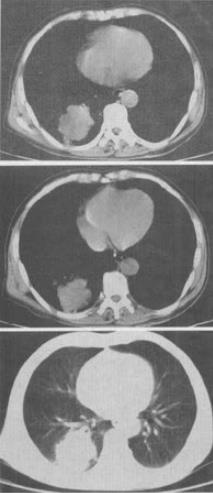

- 单项选择题1、 HIV阳性患者近来咳嗽,胸闷,胸片检查发现病变,CT检查如图,最有可能的诊断为()。

A、肺淋巴瘤

B、卡波济肉瘤

C、双肺感染

D、间质性肺炎

E、肺癌